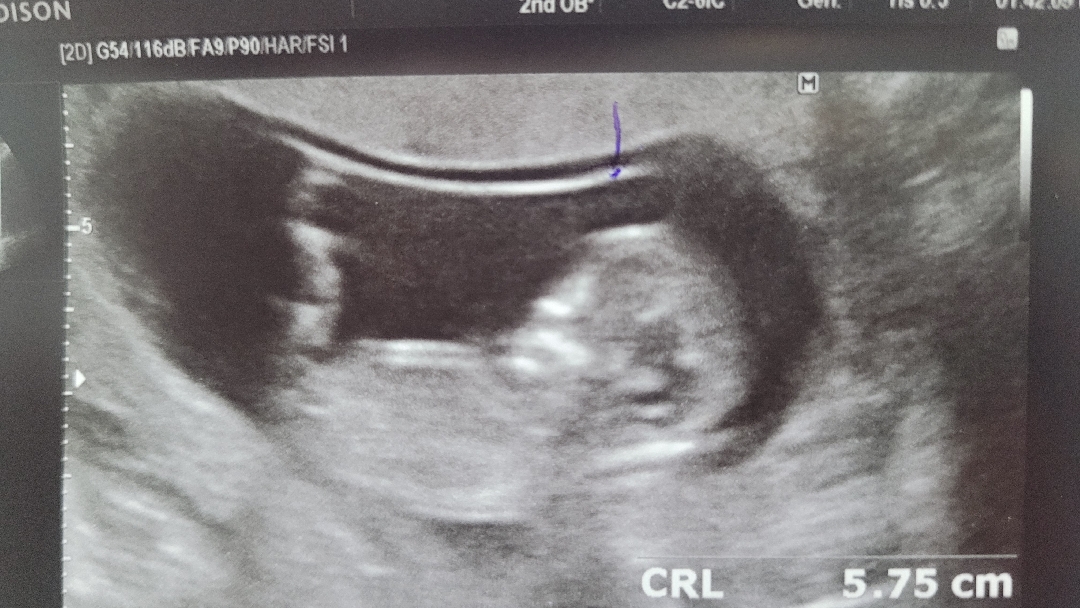

12주입니다!